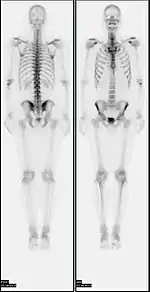

![]() A nuclear medicine whole-body bone scan. The nuclear medicine whole-body bone scan is generally used in evaluations of various bone-related pathology, such as for bone pain, stress fracture, nonmalignant bone lesions, bone infections, or the spread of cancer to the bone. | |